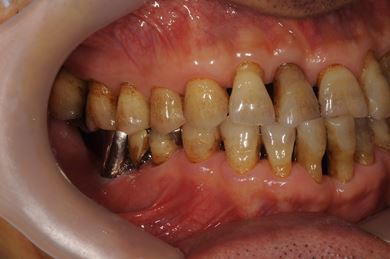

抜歯即日スピードインプラント治療+セラミック治療+歯肉遊離移植術

| 性別/年齢 | 男性 / 64歳 | ||||||||||||||||||||||||||||||||

| 主訴 | 左最奥の下部ブリッジが不安定になっており、奥2本のインプラントを考えたい。 | ||||||||||||||||||||||||||||||||

| 治療内容 | インプラント4本(抜歯即日スピードインプラント)、メタルボンドセラミッククラウン5本、ハイブリッドセラミッククラウン1本(ハイブリッドセラミック用土台1本) | ||||||||||||||||||||||||||||||||